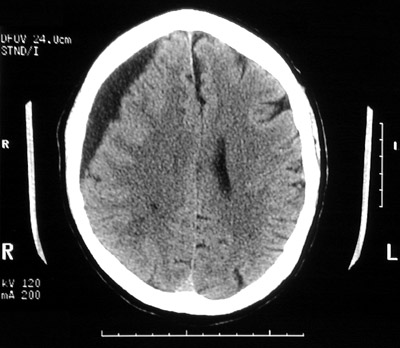

| There is a chronic subdural hematoma beneath the dura with a serrated edge interfacing with the underlying cortex. Note the effacement of the right lateral ventricular system. The view below is at a higher level near vertex. This older patient has some cerebral atrophy. |